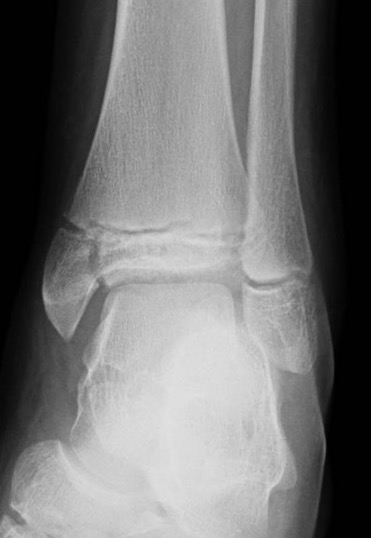

Xray

AP xray: Salter-Harris type III / Tillaux

Lateral xray: Salter-Harris Type II